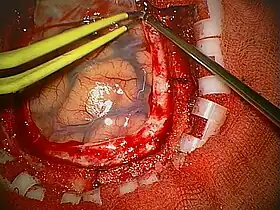

A craniotomy is a surgical operation in which a bone flap is temporarily removed from the skull to access the brain. Craniotomies are often critical operations, performed on patients who are suffering from brain lesions, such as tumors, blood clots, removal of foreign bodies such as bullets, or traumatic brain injury (TBI), and can also allow doctors to surgically implant devices, such as deep brain stimulators for the treatment of Parkinson's disease, epilepsy, and cerebellar tremor. The procedure is also used in epilepsy surgery to remove the parts of the brain that are causing epilepsy.

Human craniotomy is usually performed under general anesthesia but can be also done with the patient awake using a local anaesthetic; the procedure, typically, does not involve significant discomfort for the patient. In general, a craniotomy will be preceded by an MRI scan which provides an image of the brain that the surgeon uses to plan the precise location for bone removal and the appropriate angle of access to the relevant brain areas. The amount of skull that needs to be removed depends on the type of surgery being performed. The bone flap is mostly removed with the help of a cranial drill and a craniotome, then replaced using titanium plates and screws or another form of fixation (wire, suture, etc.) after completion of the surgical procedure. In the event the host bone does not accept its replacement, an artificial piece of skull, often made of PEEK, is substituted. (The PEEK appliance is routinely modeled by a CNC machine capable of accepting a high resolution MRI computer file in order to provide a very close fit, in an effort to minimize fitment issues, and therefore minimizing the duration of the cranial surgery.)